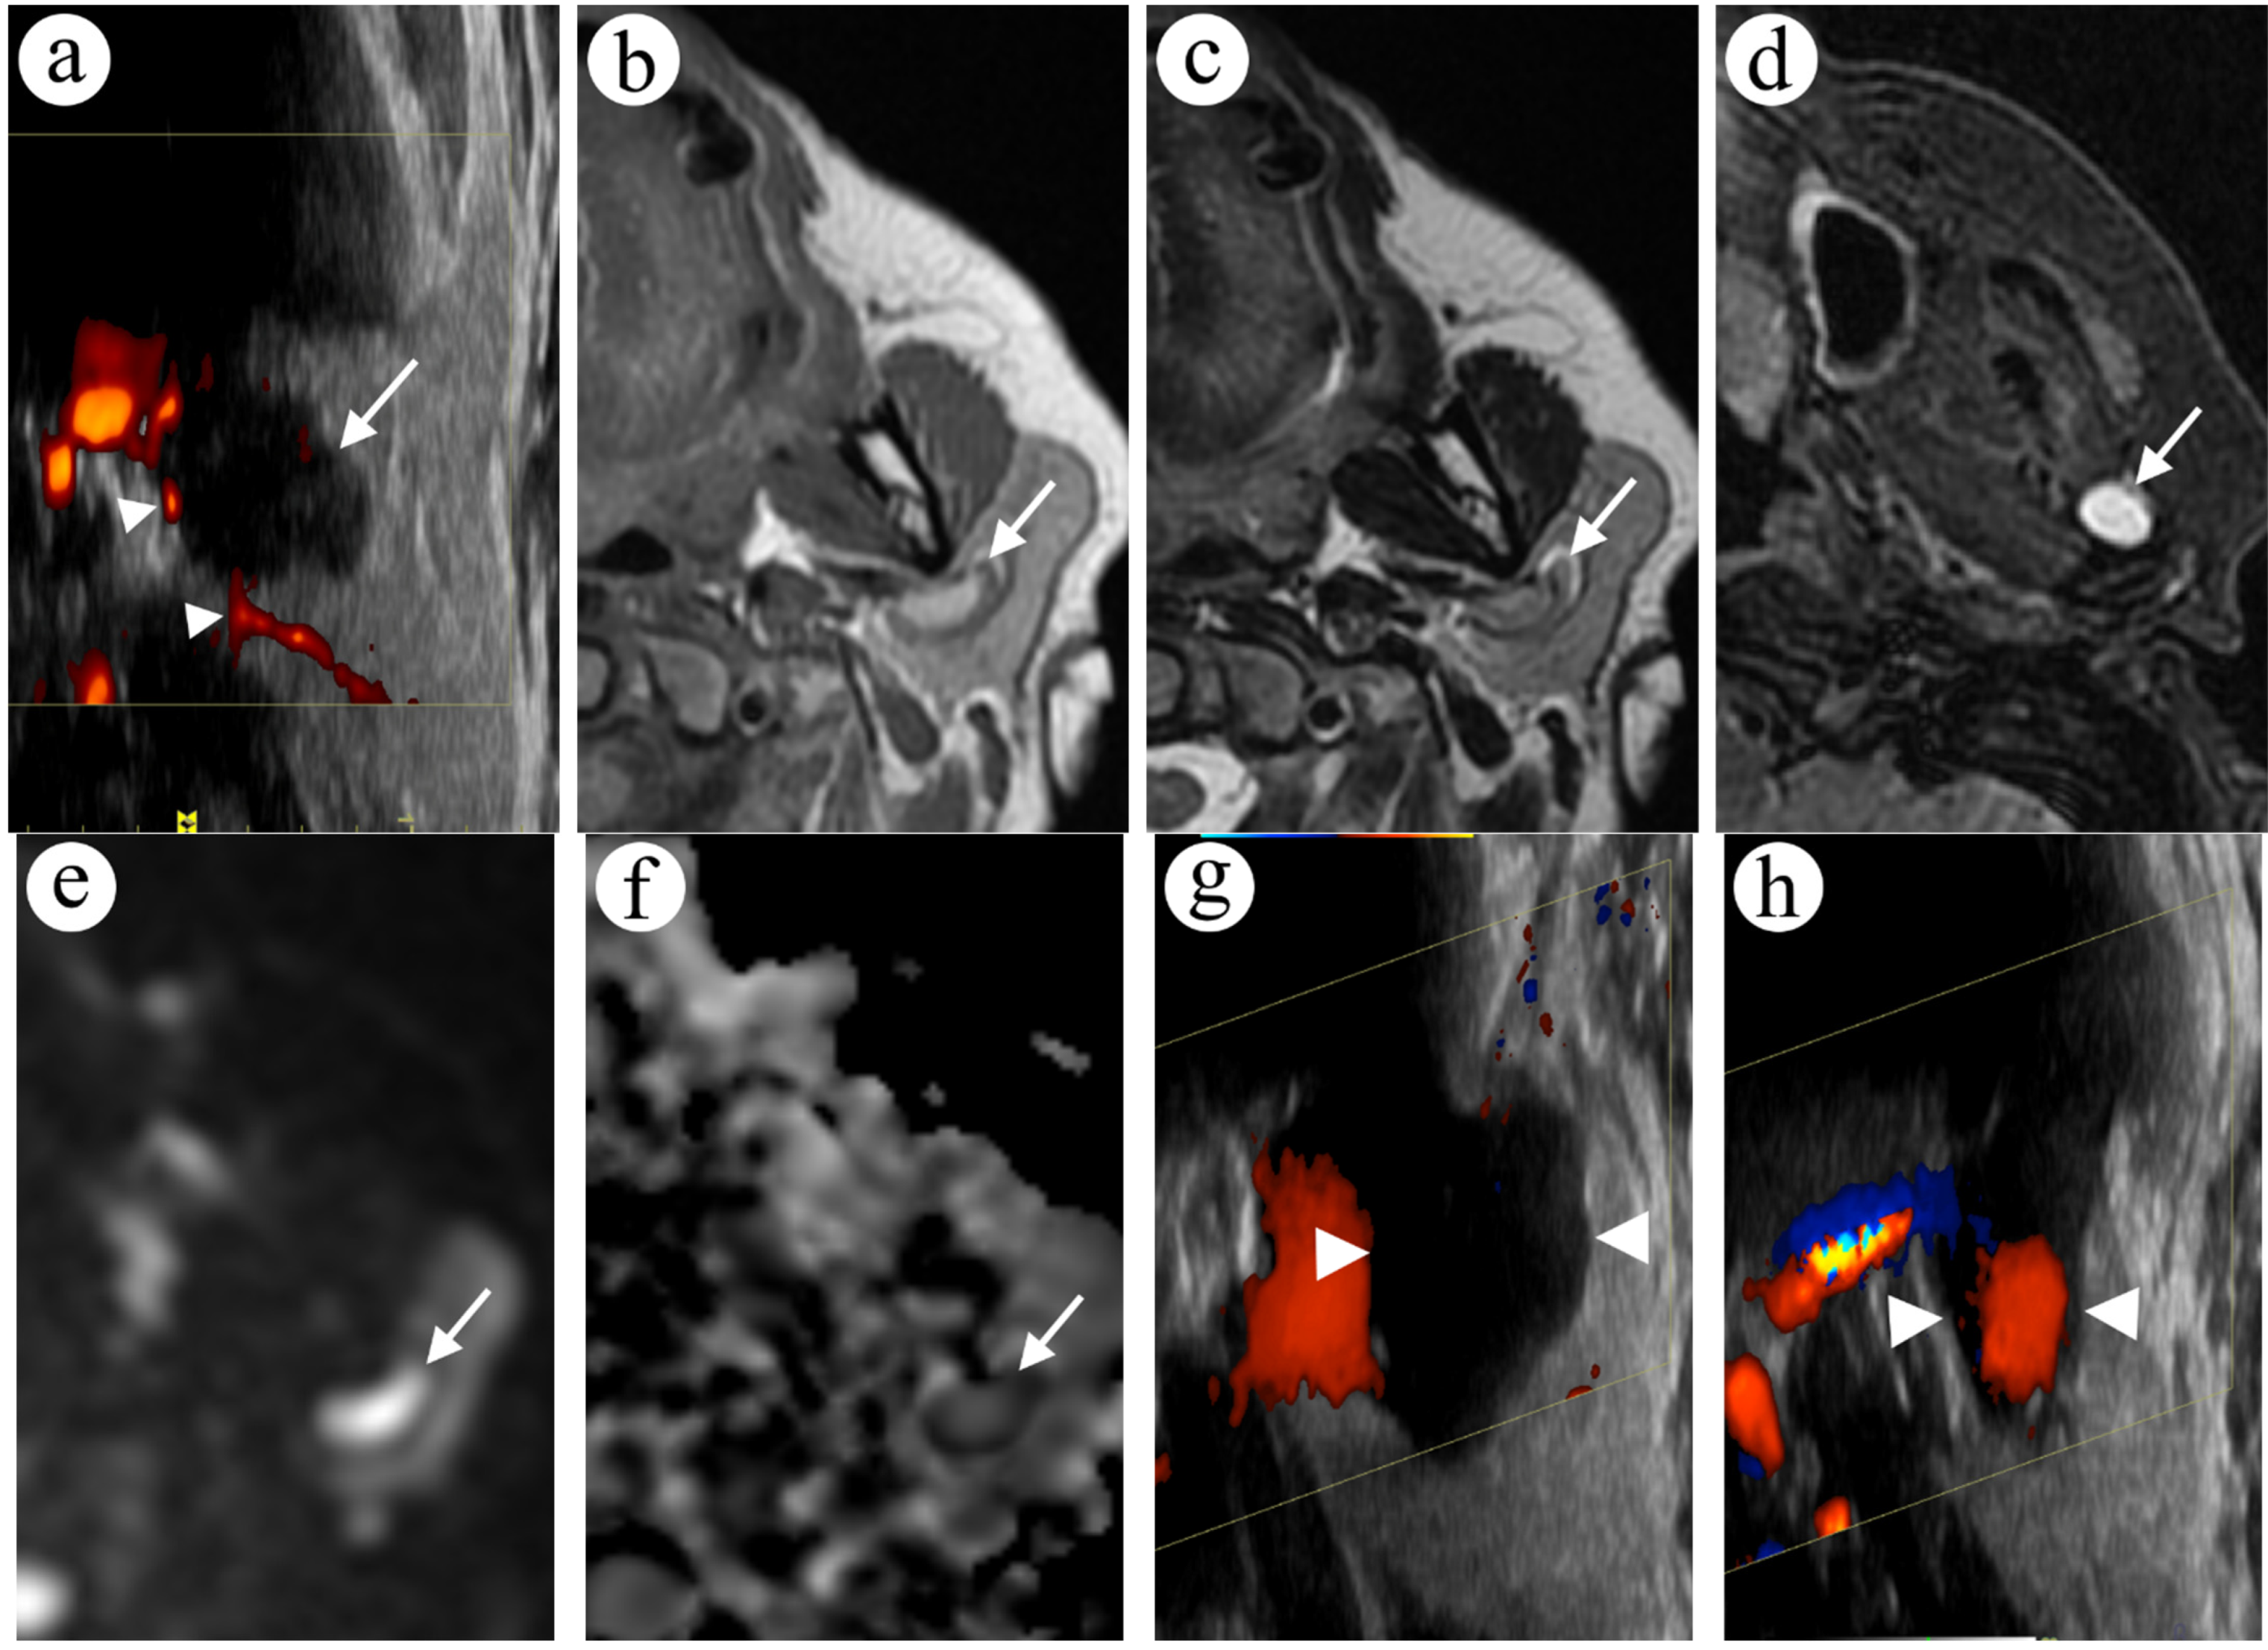

2.1. Case 1